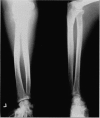

Primary lymphedema tarda is considered to be a congenital disease with delayed manifestations. We report a case of isolated lymphedema of the left upper extremity in an 88-year-old African-American male. The diagnosis of lymphedema was confirmed by lymphoscintigraphy, and appropriate diagnostic studies were done to rule out other known causes of lymphedema. Lymphoscintigraphic findings were consistent with idiopathic primary lymphedema. During the course of investigations, the patient was found to have adenocarcinoma in situ of the sigmoid colon with no evidence of metastatic spread. Based on the available data, we were unable to establish a causative relationship between colonic carcinoma and lymphedema in our patient. Therefore, this case can best be described as a case of Idiopathic primary lymphedema tarda. We emphasize the use of histopathologic examination in the diagnostic algorithm to rule out underlying malignant process only in patients with radionuclide findings suggestive of secondary lymphedema with no obvious etiology.